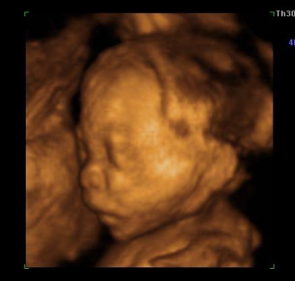

(图为四维彩超下胎儿面部)

4.系统胎儿超声检查

系统胎儿超声检查包括:除常规产前超声检查的内容外,还将对胎儿从头、面、脊柱、胸腔、心脏、腹部脏器(肝、胆、胃、肾、膀胱、肠管)至四肢做全面系统的超声检查,同时检查胎盘、脐带、羊水、子宫壁等情况,以求诊断大部分胎儿畸形。通过这种系统胎儿超声检查,可提高胎儿畸形的检出率,降低严重缺陷胎儿出生。此种检查要求较高,对超声医师、仪器设备、检查所需的时间、检查内容、检查时孕周大小均有严格要求。我科建议该检查在孕20—24周之间进行,因为此时胎儿的羊水最多,活动度较大,因此胎儿的结构显示得较清楚,可以排外更多的畸形,错过此时间将可能很难达到检查目的。